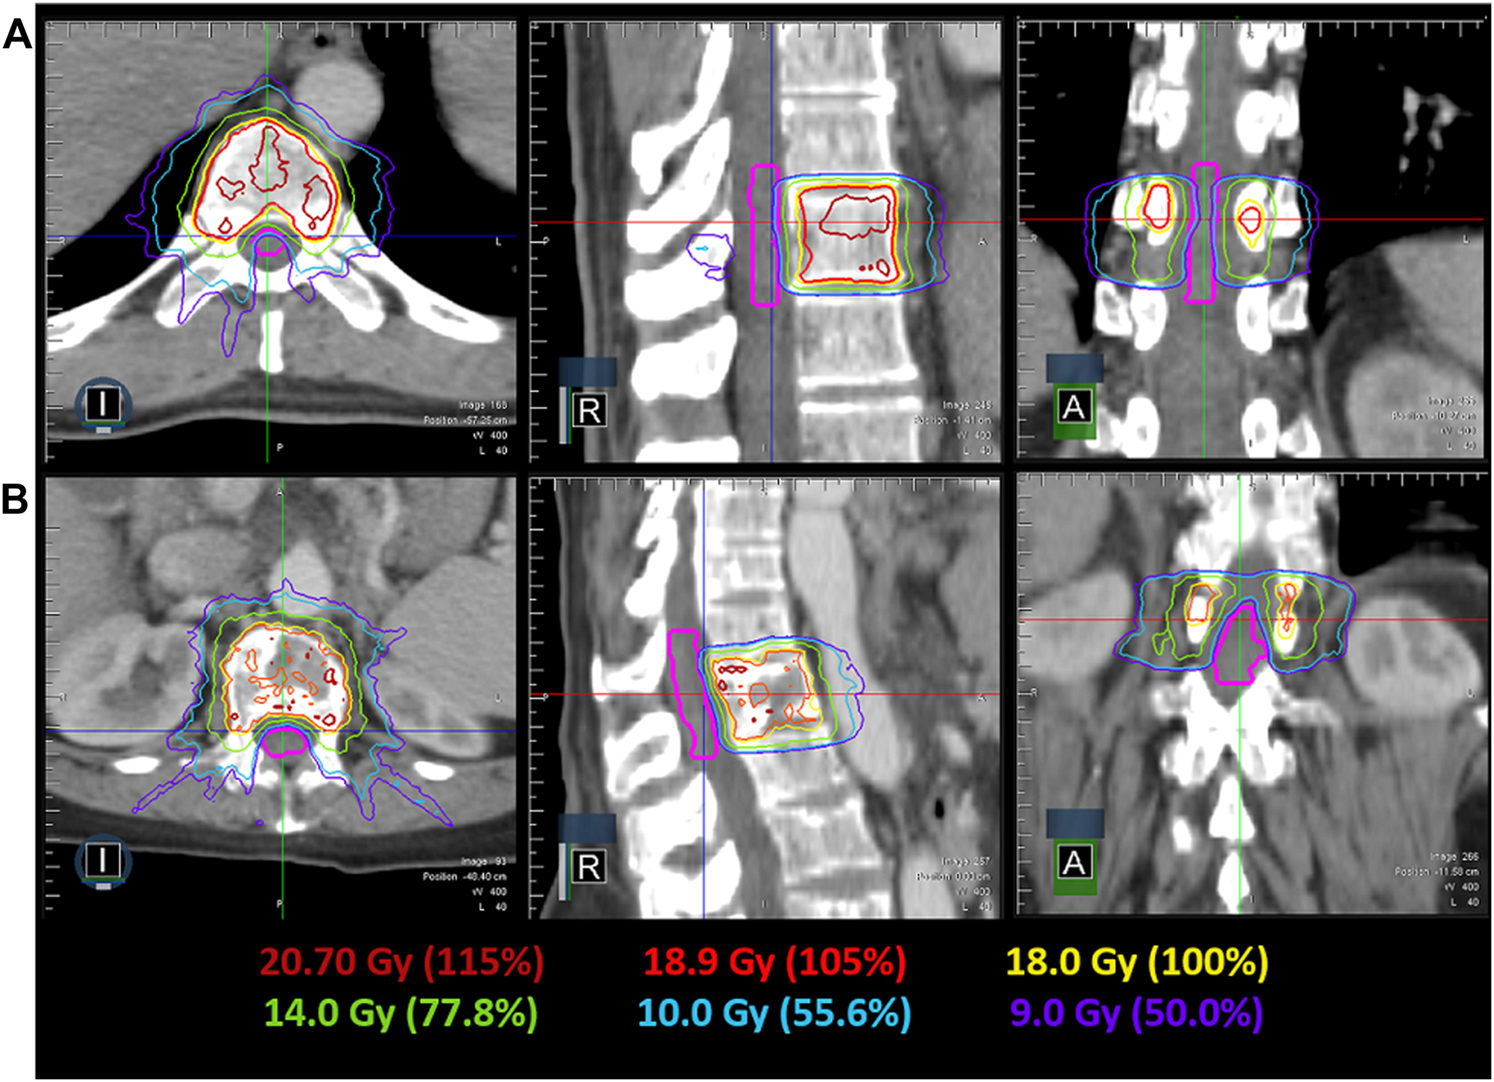

IMRT plans met all critical-tissue constraints outlined in RTOG 0631 while covering 90% of the target with the prescription dose. Plan quality metrics for each individual plan are shown in Table 1. In all cases, the spinal cord was the most limiting organ, where the largest maximum point dose encountered was 10.55 Gy, which is below the 14 Gy maximum point dose criteria. Plan quality metrics from RTOG 0631 controlling hot spots and high-dose spillage (e.g., <115% permitted outside the target volume) were achieved but provided the greatest planning challenge. Efforts were made to minimize plan complexity utilizing on average 6.5(SD = 1.6, N = 6) segments/beam, 10,716.38 MU (SD = 3,276.49 MU, N = 6) per plan and an average delivery time of 24.58 min (SD = 8.00 min, N = 6). Optimized dose distributions for a T10 and L1 vertebral body plan are shown in Figure 4. The average difference between ion-chamber measurements and treatment planning system (TPS) calculations was 3.01% (SD = 1.70%, N = 6). Respective comparison for film measurements to TPS calculations was 96.55% (SD = 2.44%, N = 6) when employing a 3%1 mm DTA global gamma-analysis criterion.

FIGURE 4. Achievable dose distribution in the axial, coronal and sagittal view for a T10 (A) and L1 (B) spine SRS plan. The spinal cord contour is shown in pink, while the relevant isodose lines are indicated by their color.